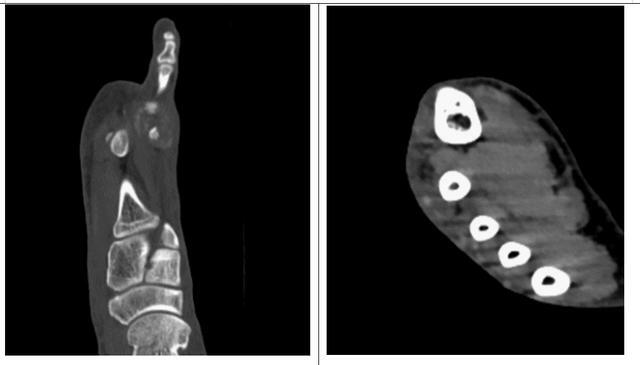

何先生的痛風石表面開起來不大,大約2cm×2cm×1cm,但是做了足部CT檢查後發現其內卻是「內藏玄機」。痛風石不僅存於足背皮膚表面,還存在第2、3跖骨頭之間,同時還發現第2跖骨頭已經出現了多處骨質囊狀破壞,骨質表面已經被痛風石所「啃食」,令人不寒而慄。

圖④患者足部CT檢查的橫截面觀(左圖)及矢狀面觀(右圖)